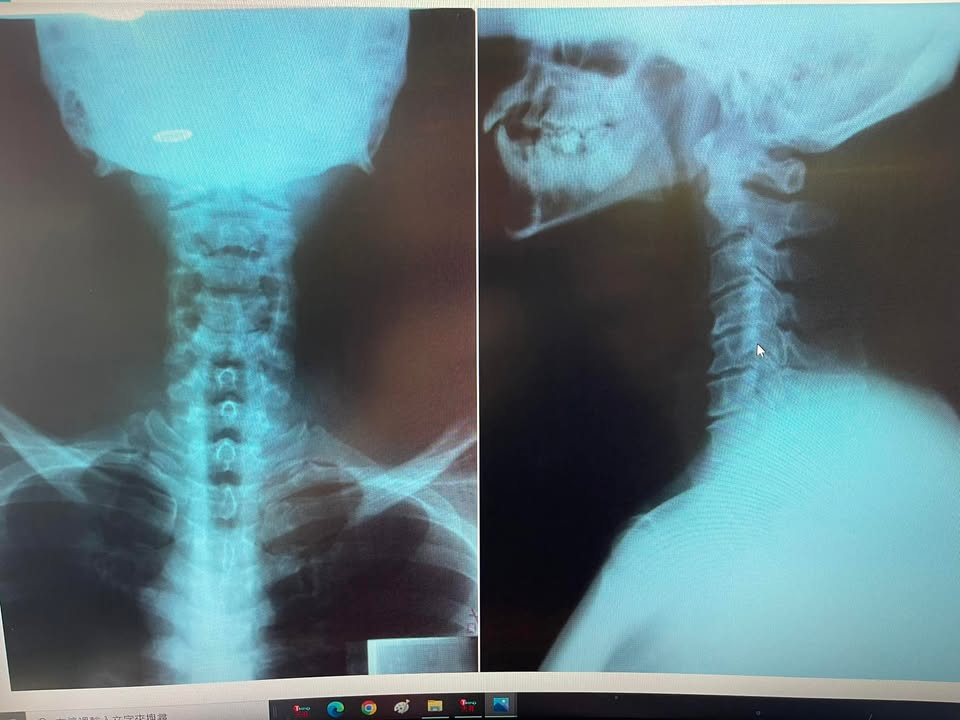

頸椎治療案例

頸椎神經根病變患者,寫的特殊的回饋。 居然直接素描我的樣子!!留下評論 💪💪💪屌針!整個人輕鬆很多😊😊😊